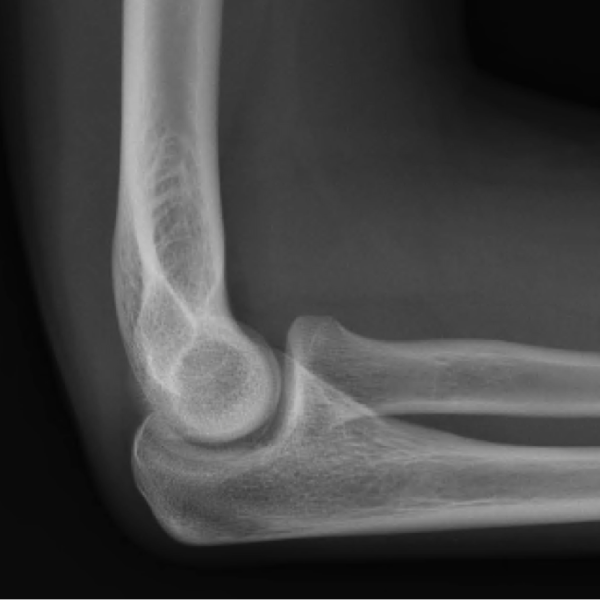

Learn the bony anatomy then test yourself